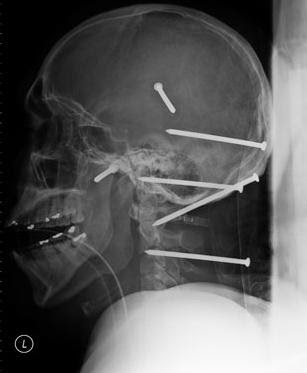

9.  Kecelakaan nailgun yang lebih dahsyat!

Pekerja  bangunan,  Isidro Mejia, jatuh dari atap, sayangnya jatuh di atas rekan  kerja lain  dengan menggunakan paku pistol. 6 paku melaju ke kepala  Mejia,  menghujum otaknya dan pangkal tengkoraknya. Ia selamat dari  operasi!